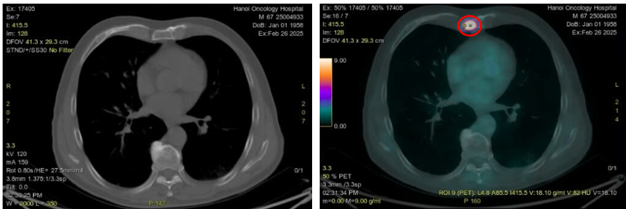

-         Chụp cắt lớp vi tính (CT) ngực:

Hình 1: Hình ảnh nốt đặc thùy dưới phổi trái kích thước 10x14mm trên của sổ nhu mô (vòng tròn màu vàng) và cửa sổ trung thất (vòng tròn màu đỏ)

Hình 2: Hình ảnh hạch trung thất ở cửa sổ chủ phổi (vòng trong màu đỏ), kích thước 8x11mm, mất cấu trúc rốn hạch

Hình 4: Hình ảnh tổn thương u phổi thùy dưới phổi trái kích thước 10x15mm trên CT (vòng tròn màu vàng) và PET/CT (vòng tròn màu đỏ) tăng chuyển hóa FDG (SUVmax: 9,8)

Hình 5: Hình ảnh hạch trung thất ở cửa sổ chủ phổi đường kính 7mm trên CT (vòng tròn màu vàng) và PET/CT (vòng tròn màu đỏ) tăng chuyển hóa FDG (SUVmax: 2,69)